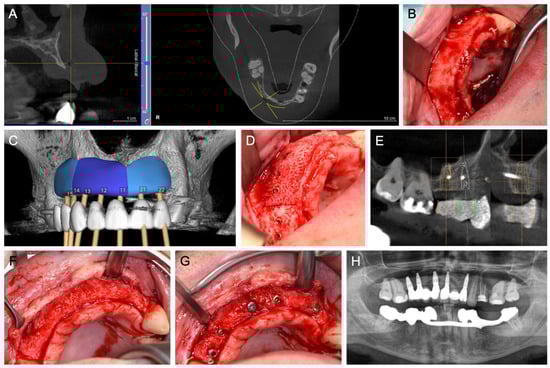

- CAD/CAM ABB—Customized, patient-specific CAD/CAM-manufactured allogeneic cancellous bone block (maxgraft® bonebuilder; botiss), designed from Cone-beam computed tomography (CBCT) data and fixed with titanium screws (Figure 4).